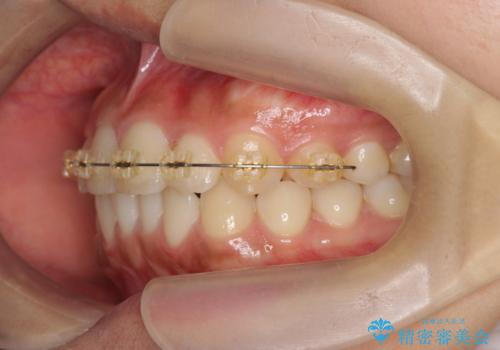

- インビザライン +部分ワイヤー矯正

上顎前歯のみの部分ワイヤー治療を約6ヶ月行い、ねじれの問題を解決したのち、マウスピース矯正で細かな歯列を整えていきます。